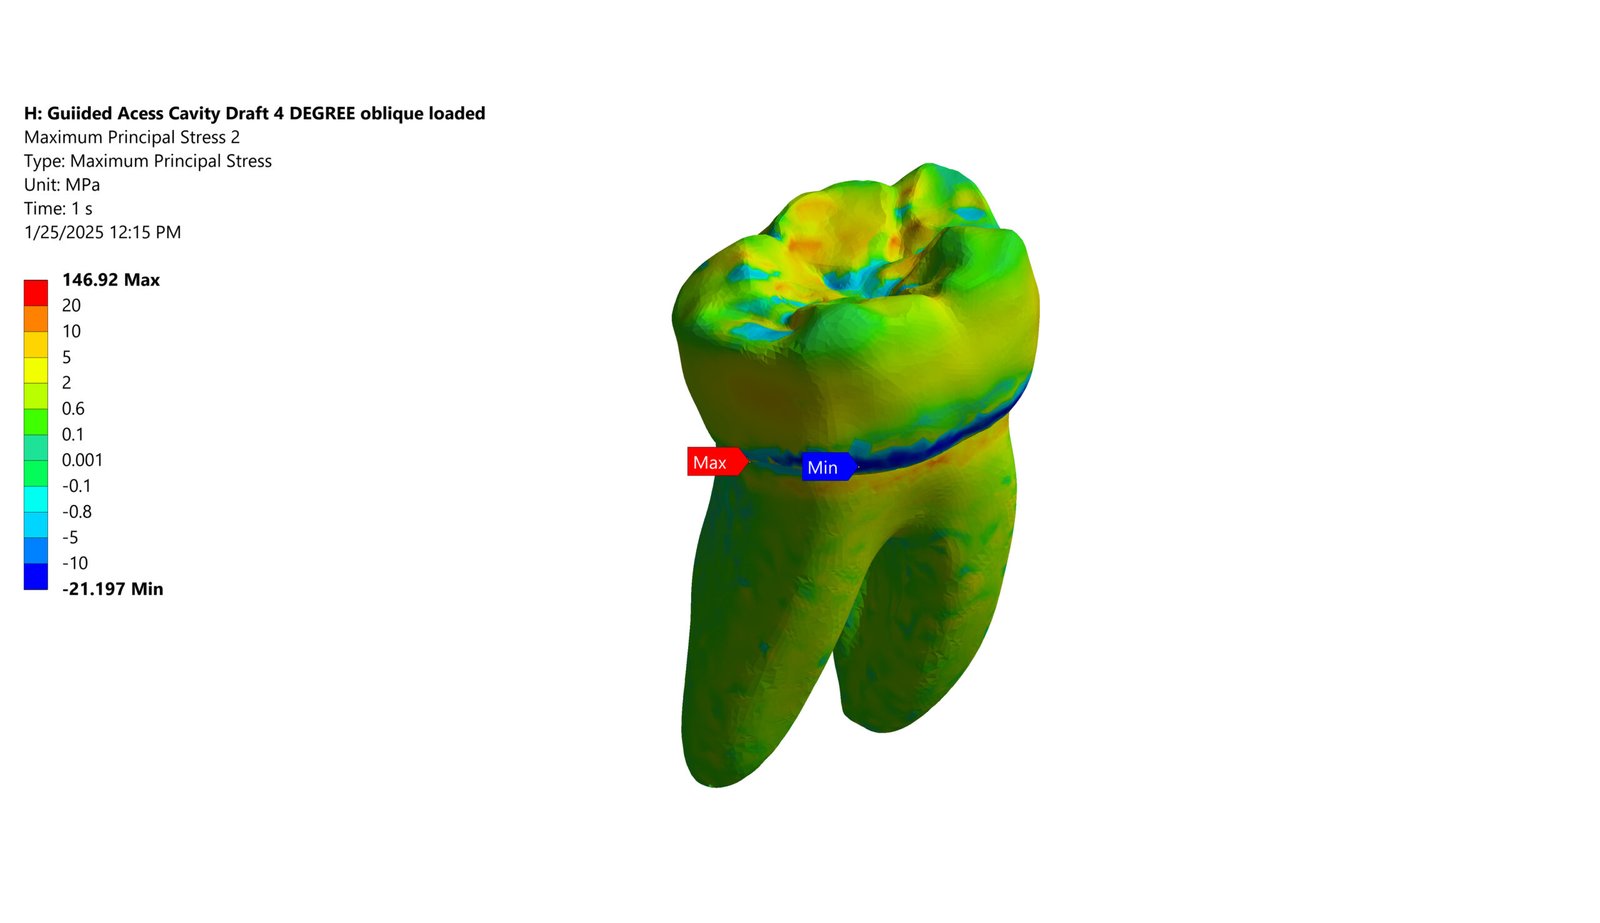

The Endodontic FEA section evaluates the biomechanical performance of root canal–treated teeth, endodontic tools, and reinforcement strategies. Through precise material characterization and micro-CT–based superimposition, we assess fracture risk, stress pathways, and instrument fatigue under various clinical scenarios. These simulations guide the selection of safer instrumentation techniques and restorative strategies. Our goal is to enhance predictability and reduce procedural complications.